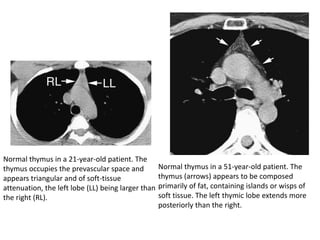

Normal thymus in a 21-year-old patient. The

thymus occupies the prevascular space and

appears triangular and of soft-tissue

attenuation, the left lobe (LL) being larger than

the right (RL).

Normal thymus in a 51-year-old patient. The

thymus (arrows) appears to be composed

primarily of fat, containing islands or wisps of

soft tissue. The left thymic lobe extends more

posteriorly than the right.

• Over theage of 25 years, the thymus is no longer recognizable as a soft-tissue structure on CT because of progressive fatty involution

Normal thymus ina 21-year-old patient. The thymus occupies the prevascular space and appears triangular and of soft-tissue attenuation, the left lobe (LL) being larger than the right (RL). Normal thymus in a 51-year-old patient. The thymus (arrows) appears to be composed primarily of fat, containing islands or wisps of soft tissue. The left thymic lobe extends more posteriorly than the right.